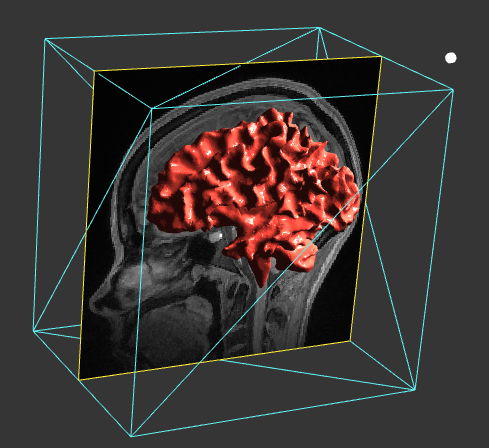

<p align="center"> <img src="https://cloud.githubusercontent.com/assets/214063/23213764/78ade038-f90c-11e6-8208-4fcade5f3832.png" width="60%"> </p>

<p align="center"> <img src="https://cloud.githubusercontent.com/assets/214063/23213764/78ade038-f90c-11e6-8208-4fcade5f3832.png" width="60%"> </p>